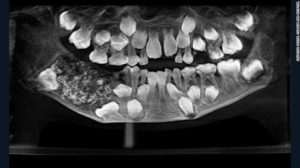

Quando os médicos examinaram e radiografaram a boca, encontraram um saco embutido em sua mandíbula cheia de "dentes anormais", disse à CNN a Dra. Prathiba Ramani, chefe de Patologia Oral e Maxilofacial do Saveetha Dental College and Hospital.

"Havia um total de 526 dentes variando de 0,1 milímetros (0,004 polegadas) a 15 milímetros (0,6 polegadas). Mesmo o menor pedaço tinha uma coroa, raiz e esmalte casaco indicando que era um dente", disse ela. O garoto foi liberado três dias após a cirurgia e deve se recuperar totalmente. Ele tem agora uma quantidade normal de 21 dentes, segundo o Dr. Senthilnathan.Condição rara

Segundo o dentista, o menino estava sofrendo de uma condição muito rara chamada odontoma composto. Ela disse que o que causou a doença ainda não está claro, mas pode ser genético ou devido a fatores ambientais como radiação, por exemplo. Os pais do garoto disseram aos médicos que haviam notado inchaço em sua mandíbula quando ele tinha apenas três anos, mas eles não podiam fazer muito a respeito porque o menino não ficaria parado ou permitiria que os médicos o examinassem. O Dr. P. Senthilnathan, chefe do Departamento de Cirurgia Oral e Maxilofacial do hospital e um dos dois cirurgiões que operaram o menino, detalhou o procedimento. "Sob anestesia geral, perfuramos a mandíbula a partir de cima", disse ele. "Nós não quebramos o osso dos lados, o que significa que a cirurgia de reconstrução não foi necessária. A bolsa foi removida. Você pode pensar nela como uma espécie de balão com pequenos pedaços dentro." Com informações da CNN. Leia tambémBrasileira busca ajuda para tratamento de condição rara em Miami